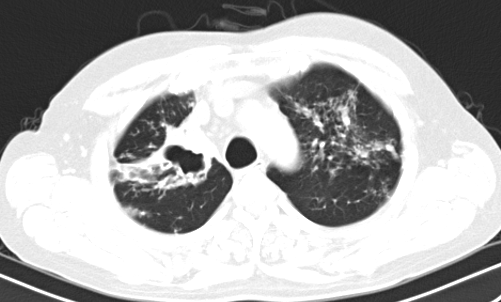

Mới đây nhất là trường hợp người bệnh Đ.Q.T (20 tuổi) ở Kim Đức, Việt Trì. Trước đó, người bệnh không hề gặp các vấn đề về hô hấp như ho khạc đờm, sốt, khó thở.

Trong quá trình kiểm tra sức khỏe tổng quát, chụp X-Quang phổi phát hiện tổn thương nên người bệnh tiếp tục được làm nội soi phế quản xét nghiệm dịch phế quản. Kết quả cho thấy người bệnh dương tính với vi khuẩn lao nên đã được điều trị lao phổi theo chuyên khoa.

| Hình ảnh thâm nhiễm đỉnh phổi trái của người bệnh Đ.Q.T - Ảnh BVCC |